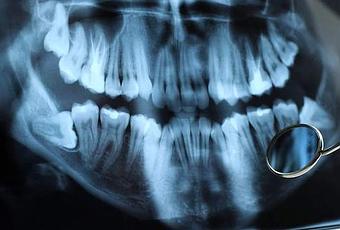

Las radiografías preoperatorias, incluidas las radiografías localizadas como las vistas peri-apicales, así como las radiografías de boca completa, se tomarán preoperatoriamente.

- La presencia de una lesión periapical radiográfica y clínicamente aparente tal como un granuloma, absceso o quiste.